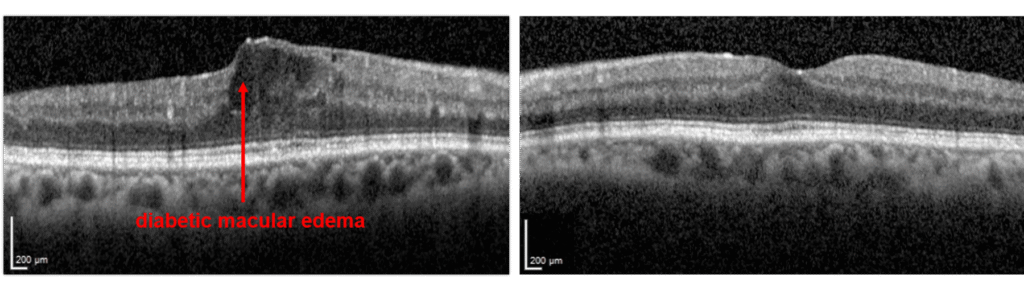

Diabetic Macular Edema (DME)

- Patients with either NPDR or PDR may develop diabetic macular edema

- Edema means “swelling”

- Blood vessels damaged by diabetes are leaky, and the fluid that leaks from these vessels accumulate in the retina

- The macula is the centermost part of the retina, which is responsible for much of high quality vision

- When diabetes causes swelling in the macula, one has “diabetic macular edema”

- Optical coherence tomography (a scan to look for swelling in the retina (DME))